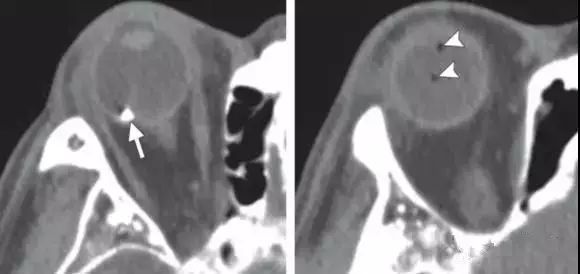

开放性眼球损伤

直接征象:眼球形态和体积异常 , 巩膜不连续;

间接征象:前房深度改变 , 眼球内异物或气体 。

鉴别诊断:脉络膜缺损-脉络膜及视网膜色素上皮层的缺损 , 常为眼球先天性组织缺损的一部分 。